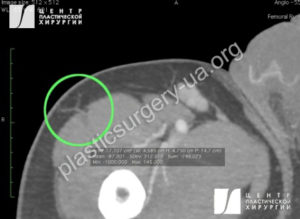

В связи с вариабельностью сосудистой анатомии проведение предоперационного планирования с использованием компьютерной томографии с ангиографией является весьма полезным для выбора как доминантных перфорантов, так и для выбора конечности, на которой планируется формирование лоскута (Рис. 3). ALT-лоскут быть может безопасно сформирован на площади от гребня подвздошной кости до латерального мыщелка бедренной кости, и от середины передней поверхности бедра (или медиального края прямой мышцы бедра) спереди и до середины бедра по задней поверхности. Эта территория кожи расположена над m. vastus lateralis, которая расположена между прямой мышцей бедра спереди и подвздошно-большеберцовым трактом сзади. Сосудистая ножка лоскута лежит глубже прямой мышцы бедра и зачастую на медиальной поверхности m. vastus lateralis. Сенсорные нервы в этой области пронизывают мышечную фасцию на 10 см ниже паховой связки и медиально от мышцы, натягивающей широкую фасцию бедра.

Рис. 3. КТ-ангиография, выполненная до разметки и формирования ALT-лоскута. На передне-латеральной поверхности бедра идентифицирован доминантный кожный перфорант нисходящей ветви, снабжающий кожу, входящую в планируемый ALT-лоскут.(обведено кругом).